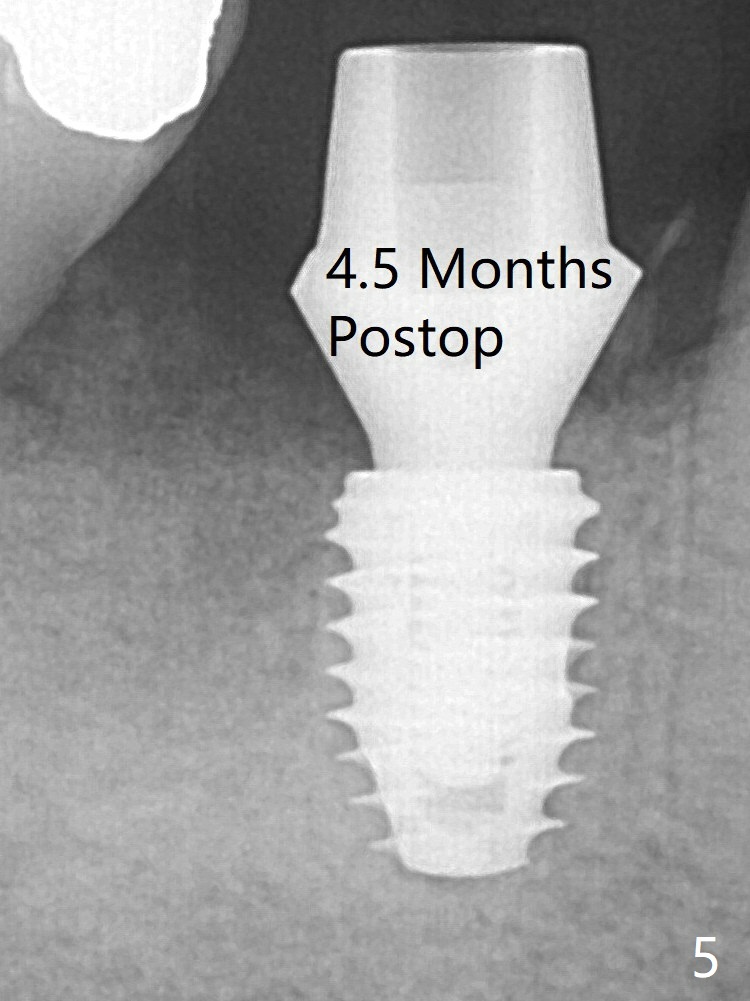

In spite of severe bone loss and 1.86 mm remaining bone after extraction of the tooth #30, a 5x7.3 mm implant achieves insertion torque of 35 Ncm with an immediate provisional (Fig.1).  Periodontal dressing is applied for additional fixation of the bone graft (*) and Osteogen plug (P).  Although the implant is placed in the mesial socket, the coronal end of the abutment is in the middle of the edentulous area.  The implant plateau seems to be covered by the bone 4.5 months postop (Fig.5).  In fact the mesiobuccal margin of the abutment is close to the corresponding crestal bone.